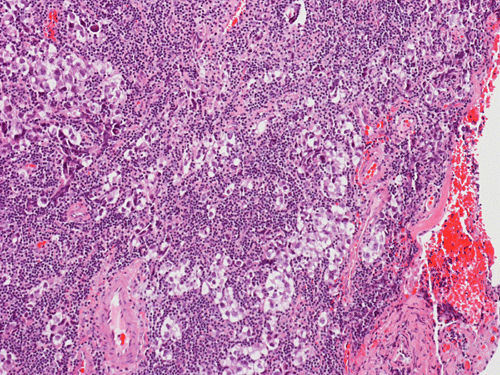

Pathology of the Case: The sample submitted for frozen section has a papillary structure which can be identified as the choroid plexus (Panel C). The center of the choroid plexus is expanded by some large cells accompanied by some smaller cells presumably lymphocytes (Panel D and E). On hematoxylin and eosin stain of the permanent sections, the tumor is composed of clusters of large cells in a background of lymphocytes. On higher magnification, the large cells have enlarged nuclei with prominent nucleoli. No trophoblasts or nor seminomatous component are identified. Immunohistochemistry demonstrated strong positive reactivity for placental alkaline phosphatase (PLAP) (Panel I) and CD117 (c-kit) in the large atypical cells (Panel J). The lymphocytes in the background are strongly immunoreactive for leukocyte common antigen (LCA) (Panel K) but negative for PLAP and CD117.

The discussion here will be limited predominantly to germinoma. Histologically, germinoma has very characteristic features heralded by large, atypical germinoma cells in a background of benign lymphocytes. The germinoma cells are usually huge, with a moderated amount of cytoplasm, and with prominent nucleoli. These cells, even though large, are rarely bizarre. The proportion of germinoma cells with lymphocytes can be highly variable. While most cases show a good mix of both component, the small biopsies yielded by endoscopic biopsy can sample in areas that are lymphocyte predominant or germinoma cell predominant areas which lead to diagnostic pitfalls. It should also be reminded that germinoma has a strong tendency to undergo granulomatous changes. Such granulomatous changes may completely efface the usually big cell-small lymphocyte classic pattern. These biopsies, however, would histologically suggest infection but the clinical history usually would not. Knowing the clinical history is often helpful. Trophoblastic cells could be seen and their presence may indicate a worse prognosis for germinomas. Non-seminomatous component such as embryonal cell carcinoma, yolk sac tumor (endodermal sinus tumor), and choriocarcinoma should also be identified if present.